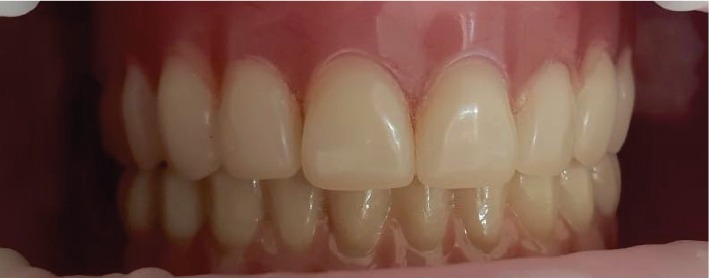

Съемные протезы верхней челюсти и нижней челюсти с опорой на имплантаты in situ.

С пациенткой было согласовано изготовление нового съёмного протеза на верхнюю челюсть. В связи с выраженными финансовыми ограничениями она отказалась от стандартного протезирования на мультиюнит-абатментах.

Поскольку имплантаты были установлены с помощью хирургического шаблона, и при планировании их располагали максимально параллельно, были заранее изготовлены трансферные проверки на титановую базу без шестигранника. Несмотря на наличие угловой установки некоторых имплантатов, после примерки трансферов в полости рта было принято решение о возможности изготовления цельнокерамического циркониевого протеза на этих титаново-циркониевых основаниях.

Надёжность данной конструкции обеспечивается тем, что протез контактирует с съёмной конструкцией на верхней челюсти, а значит, избыточного давления на нижние имплантаты не возникает.

Цельнокерамический циркониевый каркас был виртуально спроектирован после анализа всех особенностей, зафиксированных на ранее полученном STL-файле с положением сканабатментов, и затем изготовлен с применением CAM-технологий.

Пациентка соблюдает рекомендации по гигиене и проходит плановые осмотры каждые шесть месяцев.